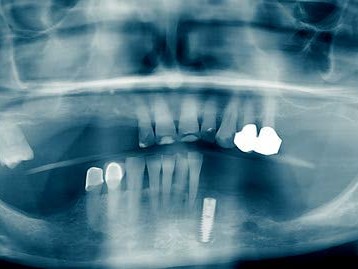

Eine 72-jährige Patientin stellte sich mit einer teleskopierenden Arbeit vor, die seit über zehn Jahren bestand. Der Teleskop-Pfeilerzahn 33 (Abb. 1) war nach Wurzelkanalbehandlung (Abb.2) aufgrund einer rezidivierenden apikalen Ostitis entfernt worden (Abb. 3). Hauszahnärztlich war ein Heil- und Kostenplan mit dem Ziel erstellt worden, sämtliche Unterkieferzähne teleskopierend zu versorgen. Dieser Vorschlag war der Patientin zu invasiv und überstieg vor allem ihre wirtschaftlichen Möglichkeiten als Rentnerin. Der Vorschlag, die bestehende Teleskoparbeit unter Insertion eines Implantates in regio 33 mit der Versorgung über das industriell gefertigte SynCone-Konuskronenprinzip zu erhalten, erschien der Patientin als eine einfache, gute und auch wirtschaftlich für sie realisierbare Alternative sinnvoll. Daraufhin wurde in regio 033 im Rahmen der Spätimplantation ein ANKYLOS C/X-A-Implantat (Durchmesser 3,5 und Länge 14 mm) inseriert (Abb. 4). Nach einer Einheilungsphase von zwei Monaten erfolgte die Implantatfreilegung. Bei der Implantatinsertion zeigte das Implantat einen Osstell-Messwert von 76 ISQ, bei Implantatfreilegung einen ISQ-Messwert von 82. Nach Überprüfung der Parallelität kam ein ANKYLOS SynCone C/ Aufbau 5° der Gingivahöhe 4,5 zur Anwendung. Dieser wurde mit 15 Ncm Drehmoment angezogen. Chairside wurde mit Unterstützung durch den Zahntechnikermeister vor Ort die ANKYLOS Degulor-Konuskappe SynCone 5° mit Retentionen eingearbeitet. Es erfolgten Nachkontrollen halbjährig. Bei der Zweijahres-Nachschau berichtete die Patientin unaufgefordert, dass sie mit der Rettung ihrer schon über zehn Jahren bestehenden Teleskoparbeit die richtige Entscheidung getroffen hatte und dass diese noch bestens in Funktion sei, wie diese selbst demonstrierte (Abb. 5-7).

Die ATLANTIS Conus-Abutments, die zugleich als industriell gefräste Primärteile dienen sollten, sowie der zugehörige Einbringschlüssel wurden versandt. Die vier Conus-Abutments wurden unter Zuhilfenahme des Einbringschlüssels inseriert (Abb. 18). Es zeigte sich eine ausgezeichnete Parallelität. Danach wurden die Abutments implantatspezifisch (Astra Tech OsseoSpeed Abb. 14: Die vier verschiedenen Implantate in situ mit ihren jeweiligen Verschlusskappen. Abb. 15: Gingiva oder Sulkusformer. Abb. 16: Gingiva- oder Sulkusformer in situ. EV mit 25 Ncm, Straumann mit 35 Ncm, ANKYLOS mit 15 Ncm, Xive mit 24 Ncm) definitiv angezogen (Abb. 19). Abschließend erfolgte eine abschließende radiologische Kontrolle (Abb. 20). Die ANKYLOS Konuskappe Degulor für SynCone 5° wurden dem Patienten mitgegeben. Der überweisende Zahnarzt war in die Planung und Gestaltung der Endversorgung von Anfang an mit Abteilungsleieinbezogen. Seitens der Autoren wurde die Einpolymerisierung der Konuskappen (Abb. 20) in die vorhandene Prothese allein aus wirtschaftlichen Erwägungen angeraten.